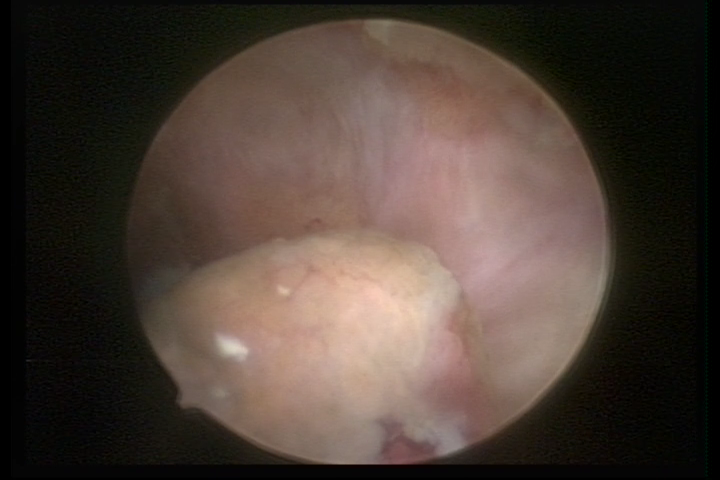

Este pode apresentar uma gama variável de aspectos macroscópicos, com aspecto pseudopolipoide; lembrando tecido cerebroide ou com reação deciduoide; a vascularização superficial é mais evidente e com vasos em formatos de saca-rolha ou espirais visualizando também a vascularização com atipias, com aumento do calibre dos vasos superficiais, pode ser encontrado também tecido em necrose, poderá haver pequenos dendritos (papilomatoso).